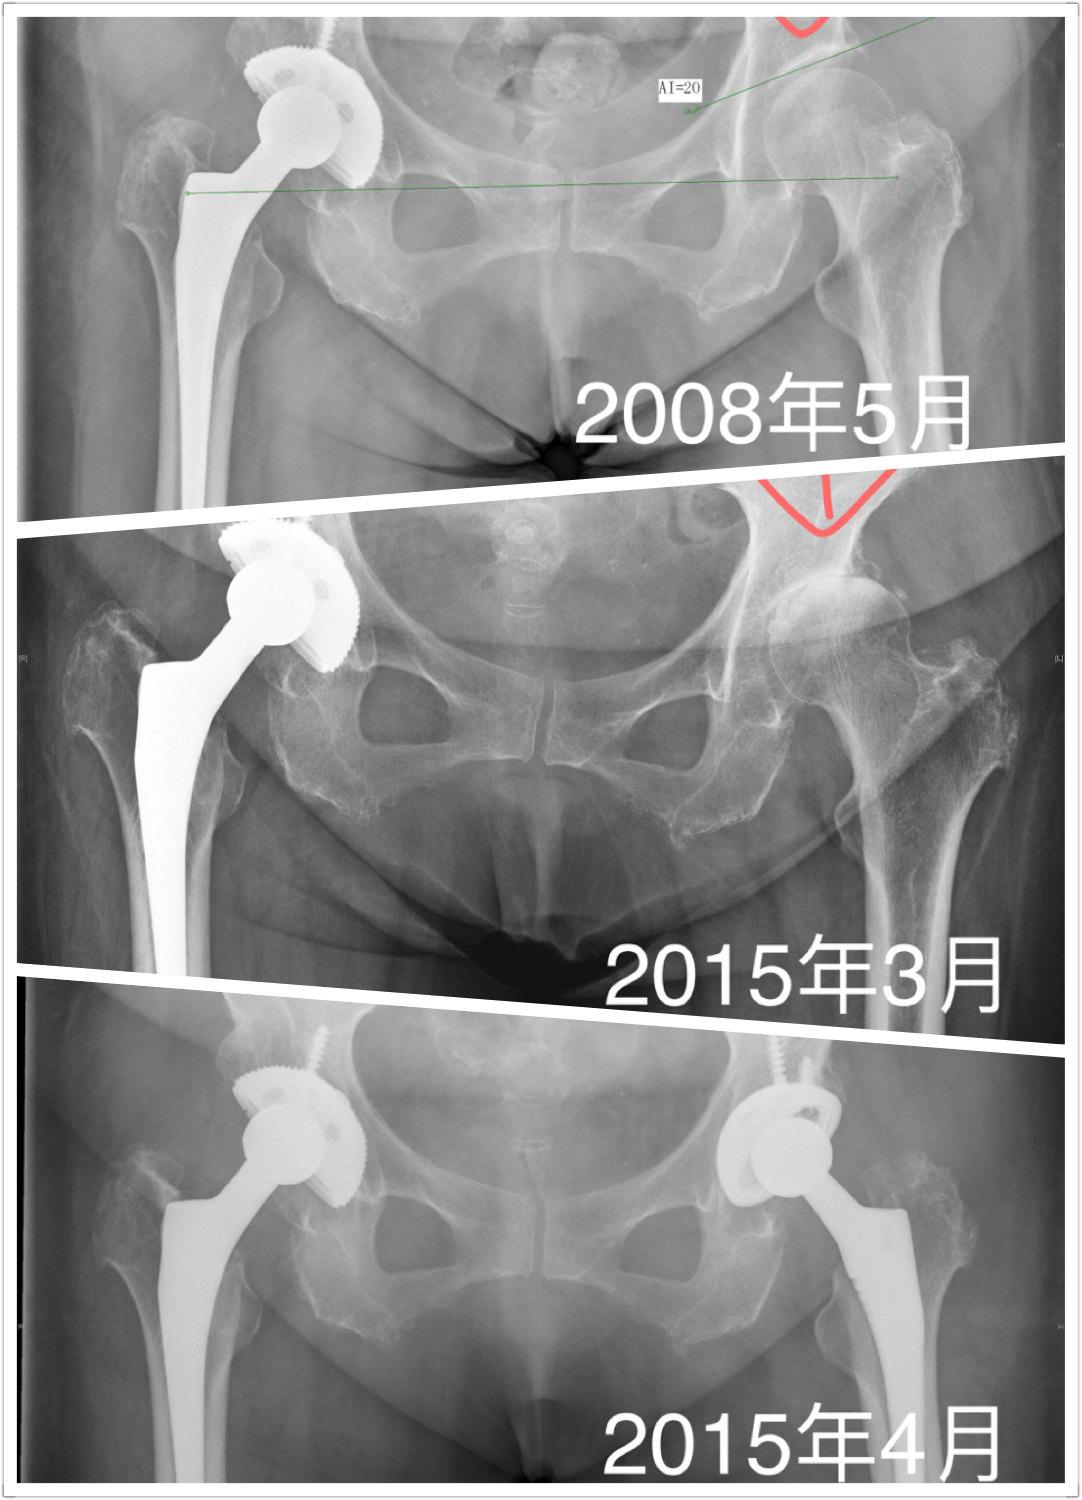

保髋成功

全面恢复股骨头供血是成功保髋核心关键